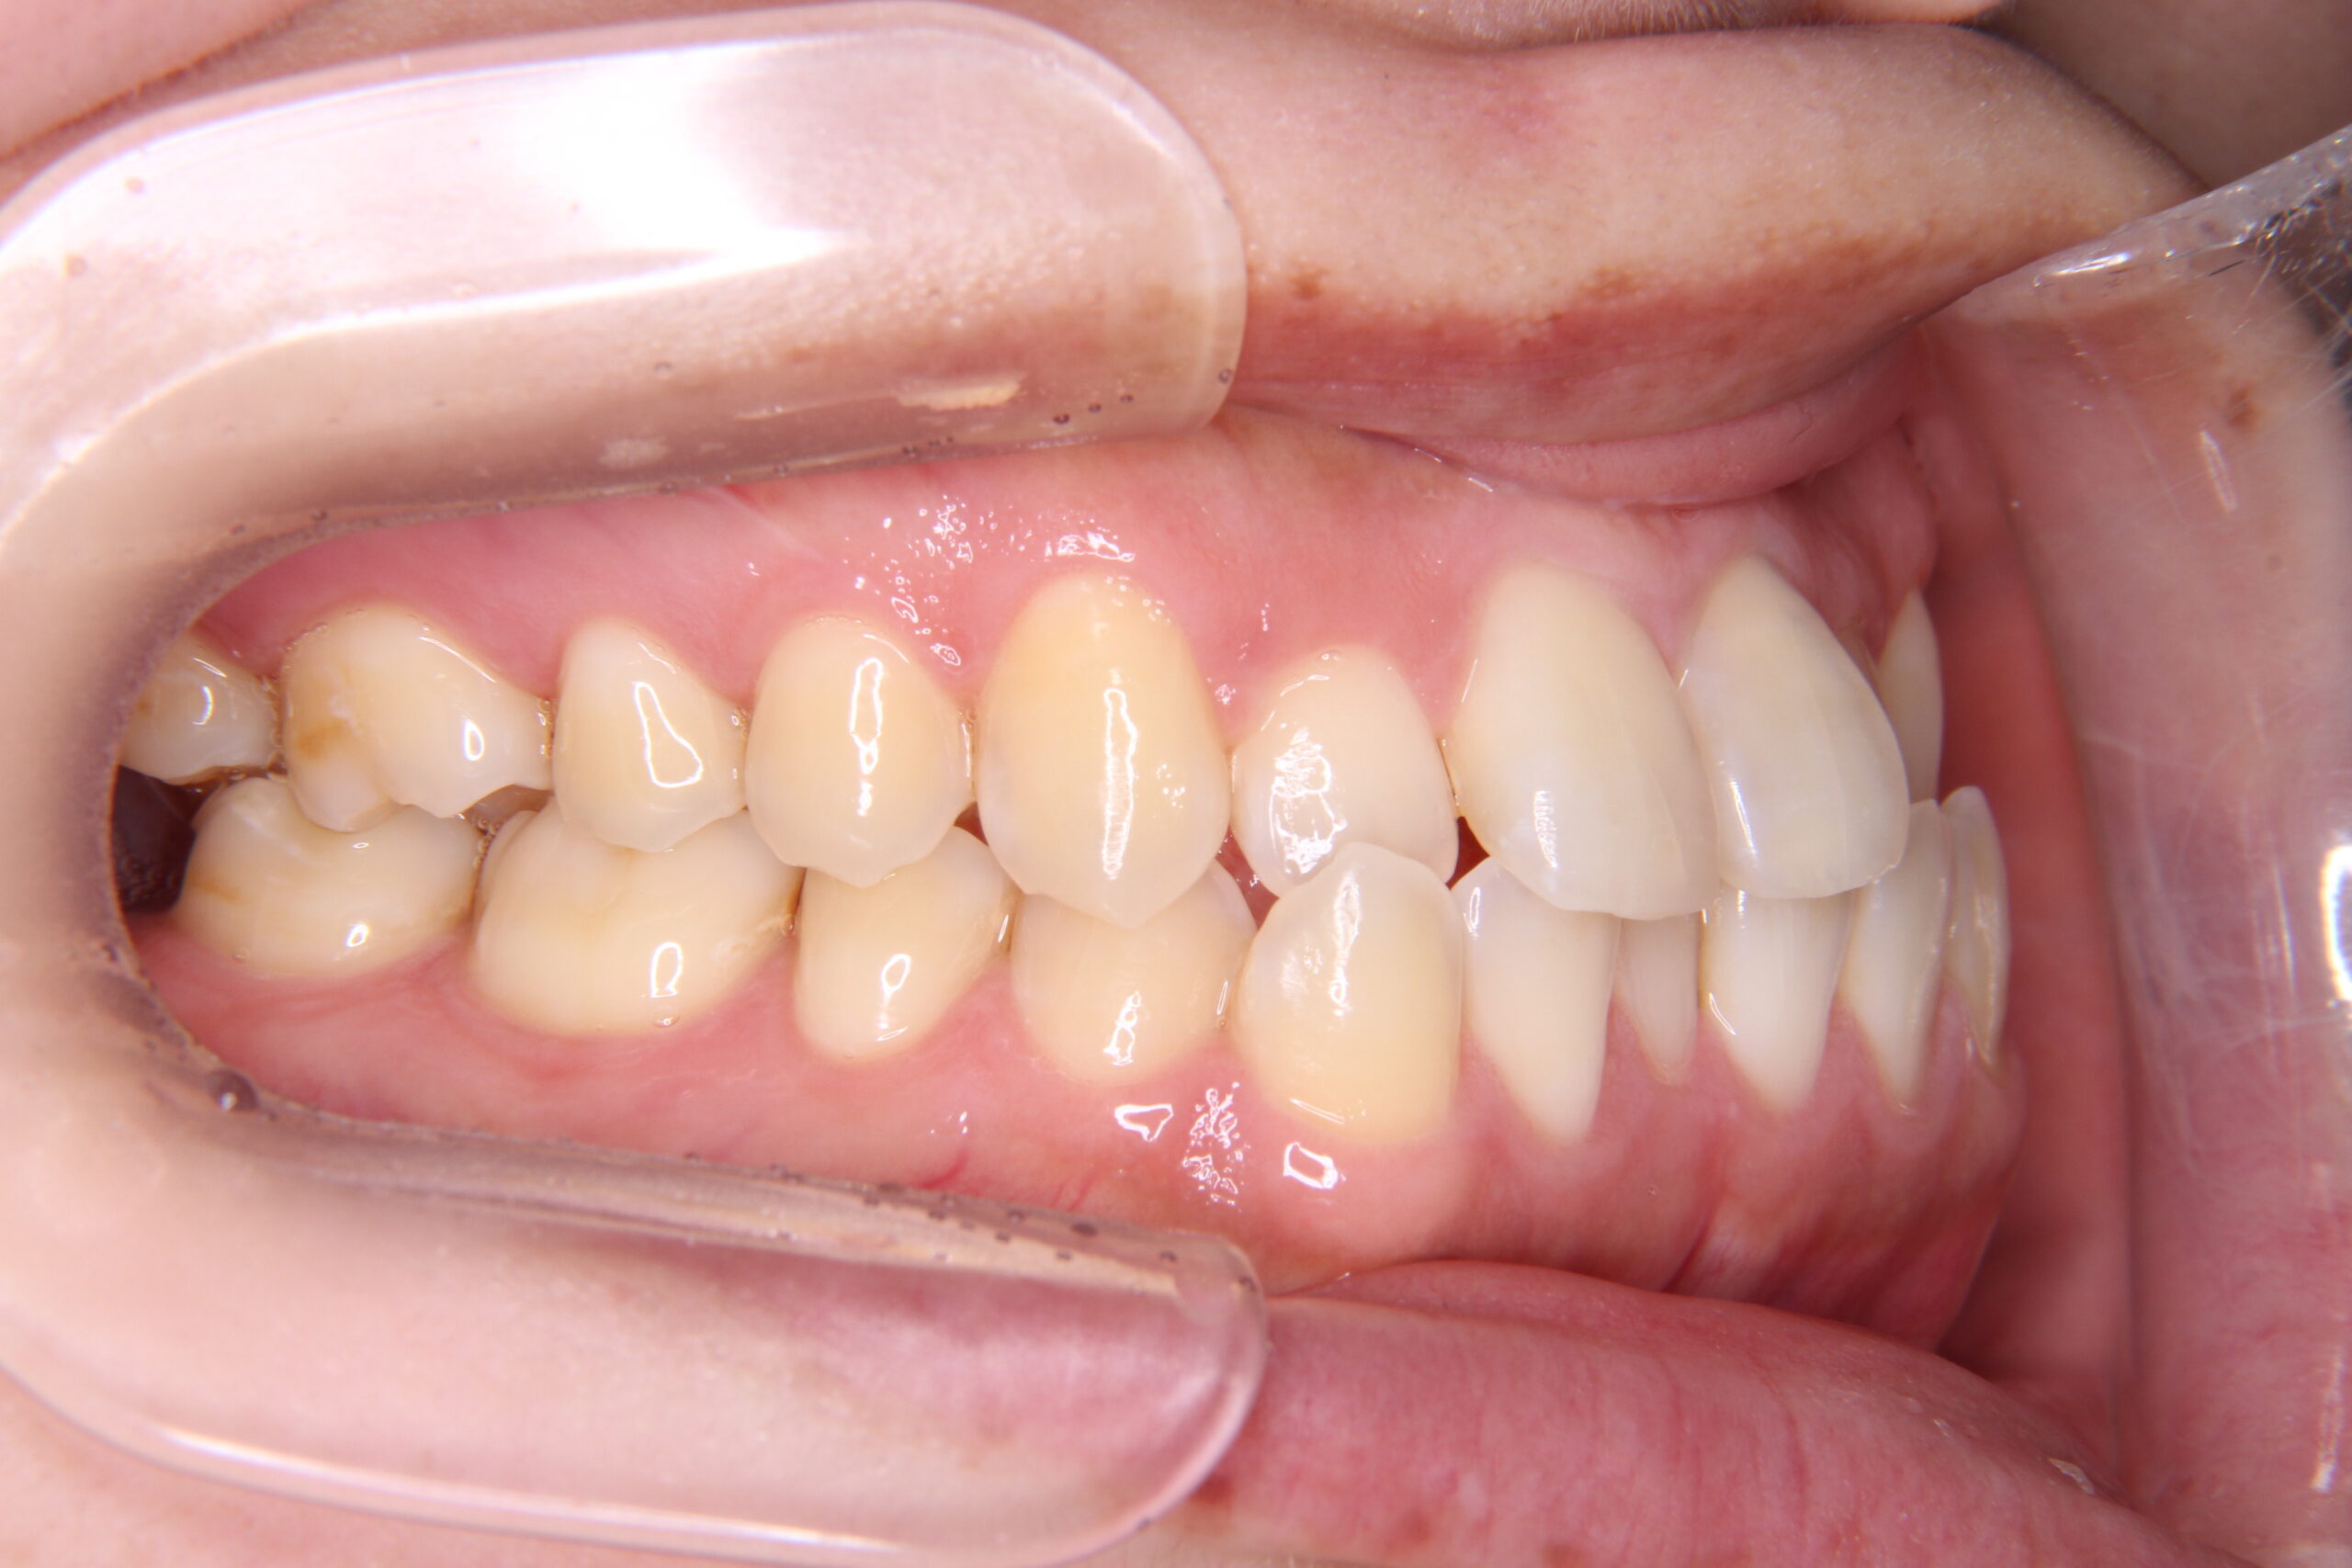

マウスピース矯正やワイヤー矯正に加え、必要に応じてアンカースクリューを活用することで、より複雑で難しい歯並びの症例にも対応しています。これにより、従来の矯正だけでは難しかった歯の移動も可能となり、幅広い治療の選択肢をご提供できます。

症例

矯正歯科専門の歯科医師が専門的な知識と確かな実績を

もとに患者様にあった最適な治療プランをご提案します。